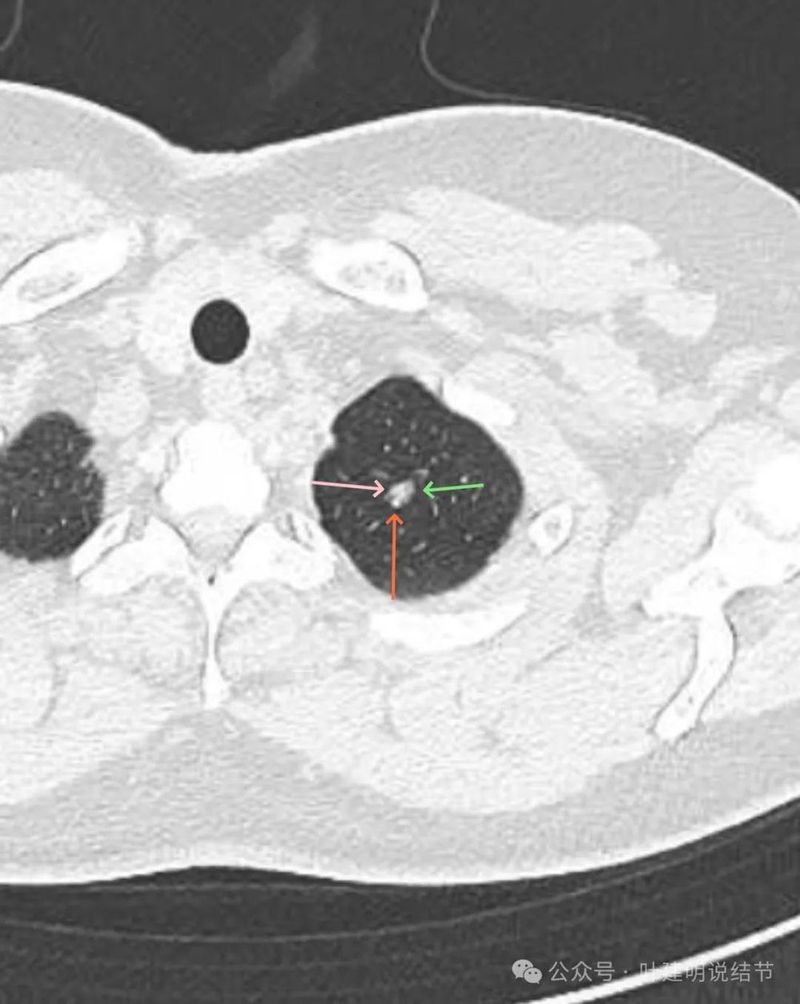

病灶出现 ,位于左肺尖,表面不平,中间有小空泡征,边缘欠光滑,灶内密度也欠均匀,整体轮廓与边界却较为清楚。

灶内细支气管扩张,边缘有小血管进入,表面不平有小棘突或毛刺,灶内密度不均,有点状高密度。